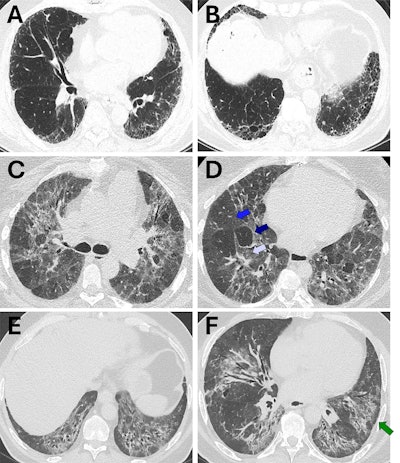

Representative cases of usual interstitial pneumonia (UIP), fibrotic hypersensitivity pneumonitis (fHP), and nonspecific interstitial pneumonia (NSIP) for which there was concordance between guideline-defined pattern (strict adherence to guidelines) and radiologist-assigned pattern (radiologist expert opinion). (A, B) Axial CT images show a case that met the criteria for guideline-defined typical UIP (2,3) and was also assigned UIP by the radiologist. The distribution is basal and peripheral, with the presence of honeycombing and reticulation and no substantial ground-glass opacity. There are no other findings that are incongruent with UIP. (C, D) Axial CT images show a case that met the criteria for guideline-defined typical fHP (2,3) and was also assigned fHP by the radiologist. The distribution is mid-upper in the craniocaudal plane and both peripheral and central in the axial plane. There is no honeycombing, but there is substantial reticulation and traction bronchiectasis. There is both lobular ground-glass opacity (white arrow in D) and hypoattenuating lung (dark blue arrow in D) alongside normal lung (blue arrow in D), forming a three-density sign. There are no other findings that are incongruent with fHP. (E, F) Axial CT images show a case that met the criteria for guideline-defined typical NSIP, defined using the 2008 American Thoracic Society workshop report (9), and was also assigned NSIP by the radiologist. The distribution is basal in the craniocaudal plane and both peripheral and central in the axial plane, with a prominent element of subpleural sparing (arrow in F). There is substantial ground-glass opacity, both pure and admixed with fibrosis. There are no other findings that are incongruent with NSIP.RSNA